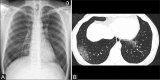

Materials and methods: In this study, patients who presented to EMS of a multispeciality hospital as suspected or confirmed Covid-19 on consecutive reverse transcriptase polymerase chain reaction (RT-PCR). CXR was examined for findings of haziness, patterns and distribution of opacities. Progression and regression of findings in serial CXR were studied and evaluated with the clinical and laboratory parameters. High resolution CT (HRCT) chest was performed initially for some patients.

Results: 756 RT-PCR confirmed COVID-19 patients were included in our study who had initial CXR. 510 (67.46%) of our patients with positive initial RT-PCR showed abnormal baseline CXR. The abnormal findings were described as haziness akin to ground glass opacities (GGO) on CT, peripheral opacities, patchy parenchymal opacities and consolidation. Peripheral opacities and lower zone distribution were the commonest pattern of CXR abnormalities with bilateral involvement. The severity of findings on serial CXR and radiographic regression was studied along with follow-up to assess response to treatment. Forty-six patients showed features of acute lung injury (ALI). Complications and new CXR findings were reported for patients who were given ventilator support.